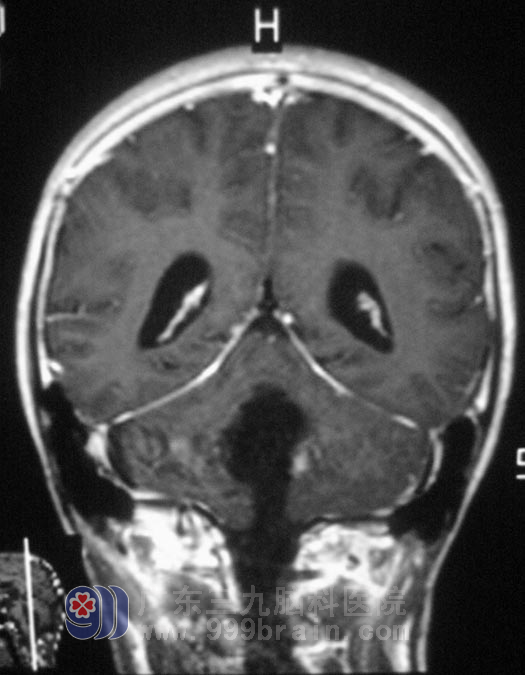

十三岁的小明,在春节后开始出现饮食不振,伴有轻微头晕、呕吐,在医院行胃肠道检查未见异常,建议调整饮食。一个月过去了,小明呕吐症状不断加重,进食量少,再次去当地医院就诊,头颅CT提示后颅窝占位,合并脑积水。小明的头痛、呕吐越来越频繁,入住广东三九脑科医院复查MR,见四脑室巨大占位,大小约3.0cm×4.0cm×5.0cm,幕上脑室扩大,梗阻性脑积水。http://www.999brain.com/

完善相关检查后,2月20日,综合神经外科 鲁明主任主刀在全麻下行四脑室占位切除术,术中显微镜下见灰白色肿瘤组织,质软,血供丰富,边界清楚,切除左侧部分扁桃体,见肿瘤与延髓交接处向上分离,边分离边切除,电凝、切开小脑蚓部约1cm,自动牵开器牵开,见灰红色肿瘤组织,伴卒中质软、血管丰富、包膜边界清晰,超声吸引器瘤内吸除部分肿瘤,止血后向上切除部分病灶后暴露四脑室顶部,向下继续分离切除肿瘤,见肿瘤与四脑室底部边界清楚,予以仔细分离切除;向左向右分离见四脑室侧孔,肿瘤分块予以切除,最后从肿瘤下方靠近延髓处切除剩余肿瘤,全切肿瘤大小约5.0cm×4.0cm×3.5cm。经过治疗后,小明头晕呕吐症状完全消失,食欲明显好转。术后病理结果为:室管膜瘤,WHO II级。